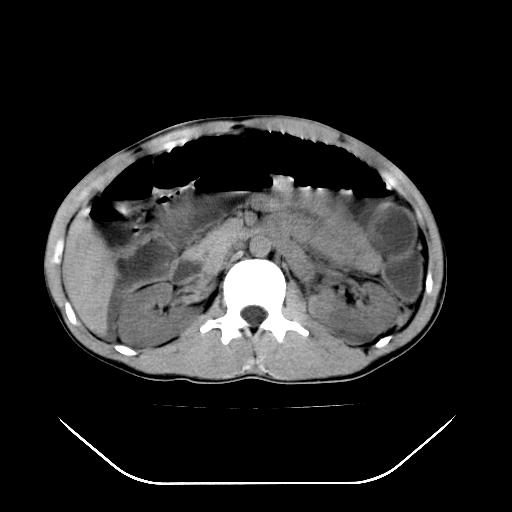

m-25y 高空堕落 12 月5号

12月7号病人尿量200ml/24h 急查双肾ct

左肾挫裂伤并肾周血肿;

肝肾间隙可见液区,建议手术探查;

支持:1、左肾挫裂伤并肾周血肿;

2、少量腹水;

3、左肾旋转不良;

4、反射性肠淤张。

反射性肠郁张是指许多原因造成肠道吸收气体和液 功能障碍,也可造成分泌功能与动力的障碍,以致肠道内有过量的气体和液体潴积,有时只有过量的气体潴积。肠道较舒张,但不扩大,或有部分肠道轻度的扩大,这种情况叫做反射性肠郁张 ,这个病人的肠管扩张太明显了。

提示有肠梗阻的可能性?

综上所述,考虑1:左肾挫伤并包膜下血肿2:少量腹腔积液3:肠梗阻的可能